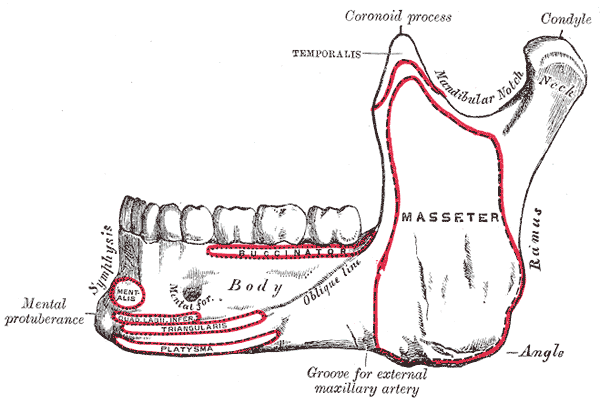

Mandible

- Symphysis & Parasymphysis Body Ramus

- Condylar process

- Coronoid process

- Mandibular foramen

- Mental n.

- 第一小臼齒下

- Mental foramen

- Lingula (小舌)

- Mental spine (頦棘)

- Sublingual g. Mylohyoid line Submandibular g.

- Oblique line

- 7,8外

- Antegonial notch

facial a./v.經過

國考毒瘤

肌肉接點